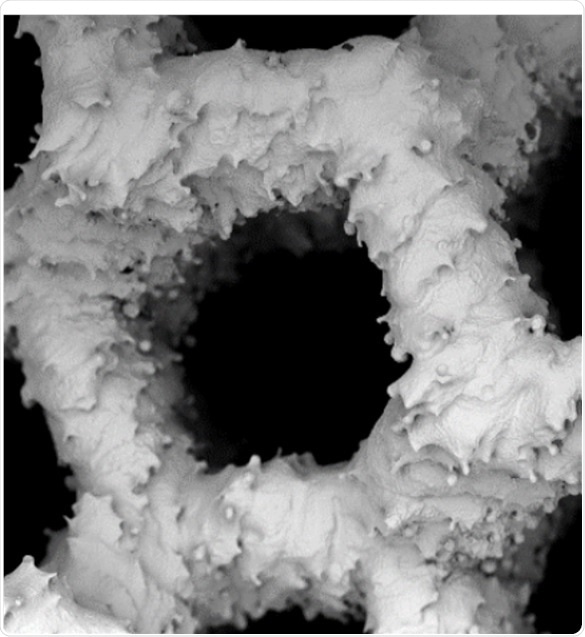

The laboratory used a SEM for this comparison, wherein the growth of human osteoblast (bone matrix cells) on BioOss, a human-like synthetic bone matrix, and on allogeneic bones after 1 week and then 3 weeks of culture, were compared. These images help concluding that the performance of the two materials is equal and confirm the efficiency of highly-processed synthetic grafts.

examples of SEM of human osteoblasts seeded on cancellous bone

Figure 1. Top row: examples of SEM of human osteoblasts seeded on cancellous bone (ACB) after 1 week of cultivation, showing embedded cells in a bone typical extracellular matrix (image magnification 555x and 1300x as indicated). Lower row: After 3 weeks of cultivation an extensive growth of the osteoblasts could be observed on the surface on BioOss® (image magnification 600x and 2840x as indicated). Images adapted1.